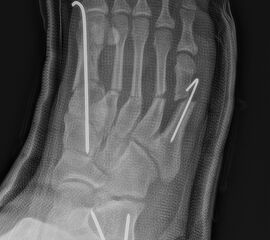

Werden komplette Osteotomien an den Zehen durchgeführt, fädeln wir die Osteotomien mit einem 1.2 oder 1.4 mm Kirschner-Draht auf, damit die einzelnen Fragmente nicht verkippen (Abb. 22).

Abb. 22 a-d: Präoperative Klauenzehen beim Jugendlichen in zwei Ansichten (a-b) und postoperative Auffädelung mit Kirschner-Drähten linker und rechter Fuß (c-d).

Nach unserer Erfahrung können komplette Osteotomien nicht so gut in einem Tapeverband stabil gehalten werden. Im Fall von Derotationen kombinieren wir einen Draht mit externen Tapezügeln, um das Ergebnis zu sichern. Die Drähte werden 2-3 Wochen belassen und anschließend in der Sprechstunde gezogen. Anschließend wird die Zehe noch 2 weitere Wochen mit Tape gezügelt (Abb. 23).